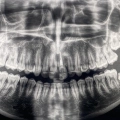

Η Ενεχειλίδου Αθηνά είναι Χειρουργός Οδοντίατρος με ιδιωτικό οδοντιατρείο στον Εύοσμο. Είναι πτυχιούχος της Οδοντιατρικής Σχολής και της Στρατιωτικής Σχολής Αξιωματικών Σωμάτων (ΣΣΑΣ) του Αριστοτελείου Πανεπιστημίου Θεσσαλονίκης, με μετεκπαίδευση στην Εμφυτευματολογία από το New York University των ΗΠΑ. Κατά τη διάρκεια της επαγγελματικής της πορείας, εργάστηκε ως Οδοντίατρος στη Γναθοπροσωπική Χειρουργική Κλινική του 401 Γενικού Στρατιωτικού Νοσοκομείου Αθηνών και στο Οδοντιατρείο Φρουράς Αθηνών (ΟΦΑ). Επιπλέον, διετέλεσε Διευθύντρια του Οδοντιατρείου Φρουράς στο ΣΤΕΠ Κομοτηνής, καθώς και Υποδιευθύντρια του Οδοντιατρείου Φρουράς στο 212 Κινητό Χειρουργικό Νοσοκομείο Ξάνθης. Σήμερα, παράλληλα με το οδοντιατρείο της, εργάζεται ως Επιμελήτρια στο 424 Γενικό Στρατιωτικό Νοσοκομείο Εκπαιδεύσεως. Επιπροσθέτως, είναι μέλος του Οδοντιατρικού Συλλόγου Θεσσαλονίκης. Στο οδοντιατρείο της, η κυρία Ενεχειλίδου παρέχει ολοκληρωμένες υπηρεσίες για την πρόληψη, διάγνωση και αποκατάσταση της στοματικής υγείας. Πραγματοποιεί καθαρισμό και στίλβωση δοντιών, σφραγίσματα, λεύκανση, τοποθέτηση στεφανών και γεφυρών, καθώς και εμφυτεύματα και bonding δοντιών, εξασφαλίζοντας ένα υγιές και αισθητικά άρτιο χαμόγελο.